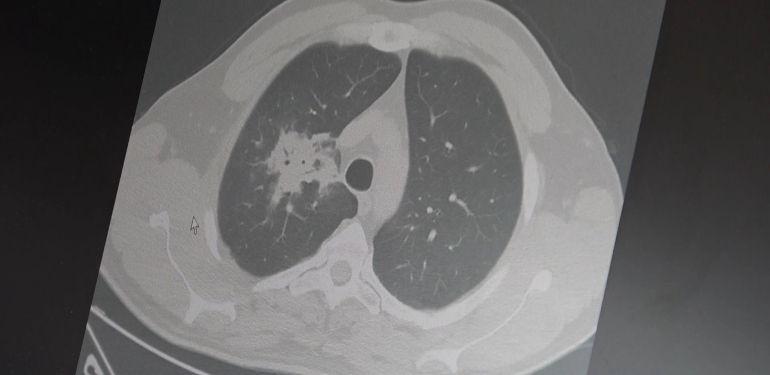

Göğüs Hastalıkları Uzmanı Prof. Dr. Şevket Özkaya, elektronik sigaraların 2000'li yılların başında geleneksel sigaraya göre daha temiz, daha az kokulu ve daha güvenli bir alternatif olarak pazarlandığını, milyonlarca kişi tarafından hızla benimsendiğini hatırlattı.Kullanıcıların yıllardır "Zararı var mı, sigaraya göre daha...